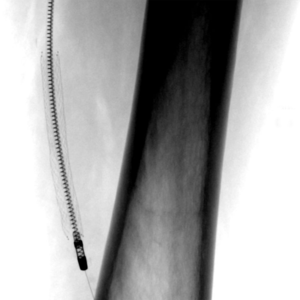

3. Stentimplantation – Einsetzen eines Stentes/ Gefäßstütze

Nach der Gefäßweitung kann durch Einrisse in den inneren Ablagerungen oder durch die Elastizität der Gefäßwand die Weitung nur ungenügend erfolgreich sein. Zur Stabilisierung des Befundes wird dann in diese Gefäßregion ein Stent eingesetzt. Dieser besteht aus einem feinen starren oder flexiblen Edelmetallgeflecht und kann auch mit Medikamenten gegen die Arteriosklerose oder zur Verhinderung der Bildung von Blutgerinnseln beschichtet sein.

Unter bestimmten Bedingungen, v.a. bei Verletzungen der Gefäße mit daraus resultierender Blutung oder lokalen Gefäßerweiterungen, werden Stents mit einer Ummantelung eingesetzt, die die Gefäßwand abdichten oder die Erweiterung überbrücken.